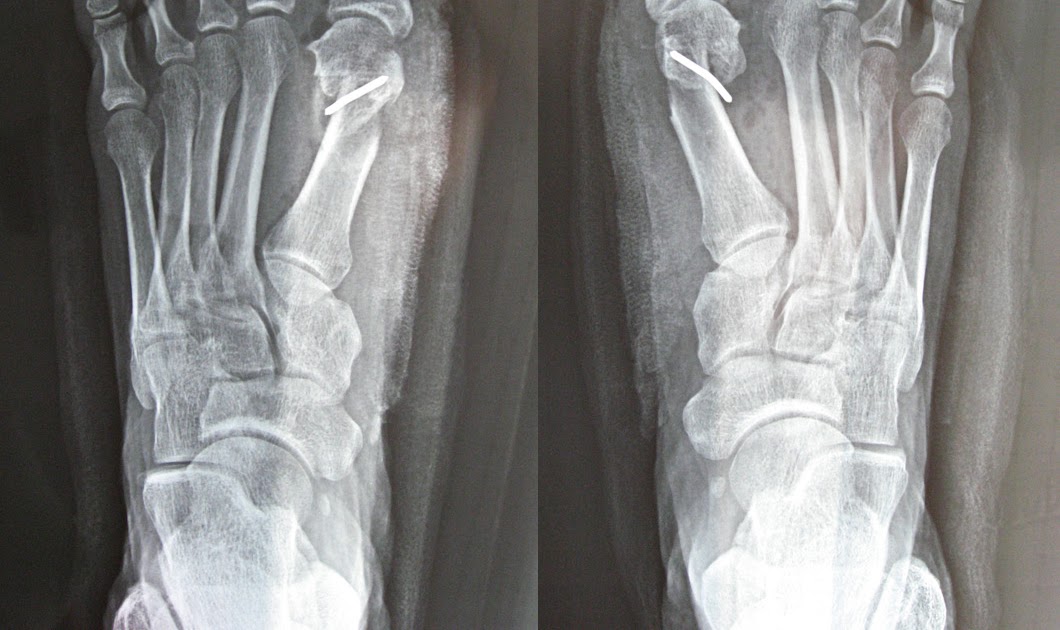

Bunion Surgery X Ray Before And After . view 8 before and after bunion surgery photos, submitted by real doctors, to get an idea of the results patients have seen. Some services may not be offered in our offices. Perform an electrocardiogram to check your heart function. After the procedure (right), the bump has been shaved, but the toe deformity remains and is. your doctor will: You will also need to see your primary care provider for tests to make sure that it would be safe for you to have surgery. after bunion surgery, adhering to a structured physical therapy program is essential for a successful recovery. The arrow shows a large bunion and crooked big toe. Your doctor will guide you through your treatment options. This guide is for informational purposes only.

Before & After xrays double bunionectomy on 1st & 5th toes, double Bunion Surgery X Ray Before And After Perform an electrocardiogram to check your heart function. The arrow shows a large bunion and crooked big toe. This guide is for informational purposes only. view 8 before and after bunion surgery photos, submitted by real doctors, to get an idea of the results patients have seen. after bunion surgery, adhering to a structured physical therapy program is. Bunion Surgery X Ray Before And After.